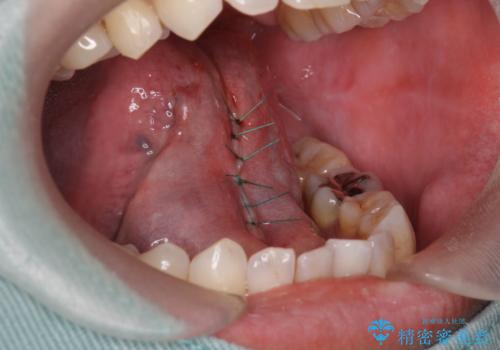

- 舌を動かしにくいとのことで来院されました。

舌の裏側にある舌小帯という部分が短い状態だったため、舌小帯の切除をすることとなりました。

術後の治りも良く、以前よりも話しやすくなったと大変喜んでいただけました。